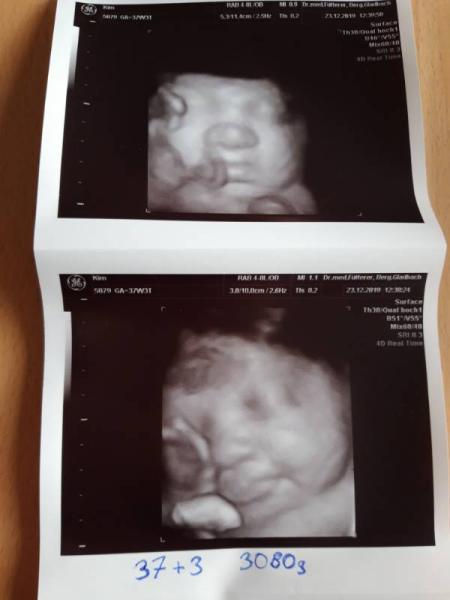

Heute war mal wieder Untersuchung. Und wir sind schon ganz verliebt in die kleine Maus Bei 37+3 hat sie schätzungsweise 3080g Alles im grünen Bereich. Es kann jederzeit losgehen aber mein Arzt meinte eventuell nach Weihnachten. Wir sind gespannt und jeder Tag den sie noch bleibt ist gut für sie. Wir freuen uns auf jeden Fall wenn es losgeht und wir sie in unseren armen halten dürfen Wir wünschen euch allen frohe Weihnachten und ein schönes Fest mit euren liebsten. Lg Mel

Bild zu Untersuchung :) 38 Woche - Forum für Januar - Mamis